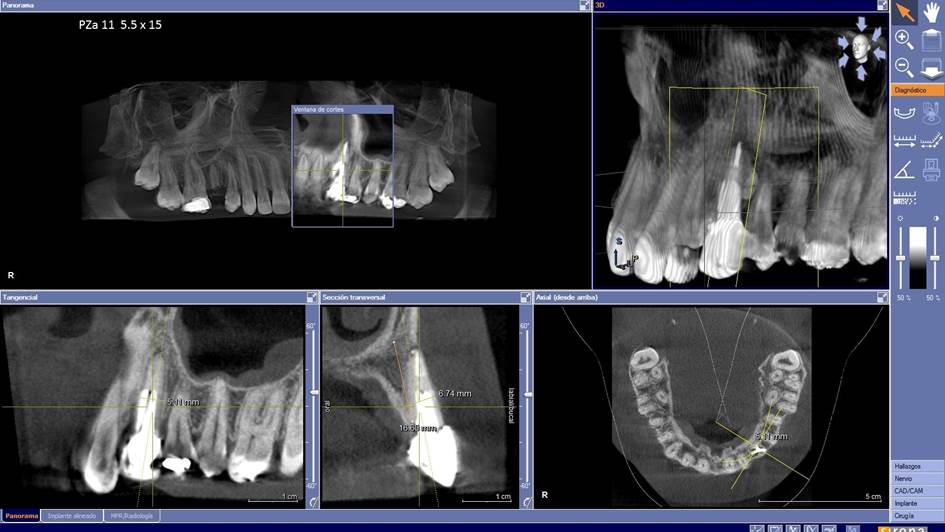

Clinical case: Extraction, immediate implant placement, & provisionalization

- Courtesy of Dr. Iulian Filipov, Romania -

Keywords

AnyRidge, R2GATE, guided surgery, immediate placement, immediate provisionalization, initial stability, Dr. Iulian Filipov, #25, maxillary posterior, immediate loading, Mega ISQ